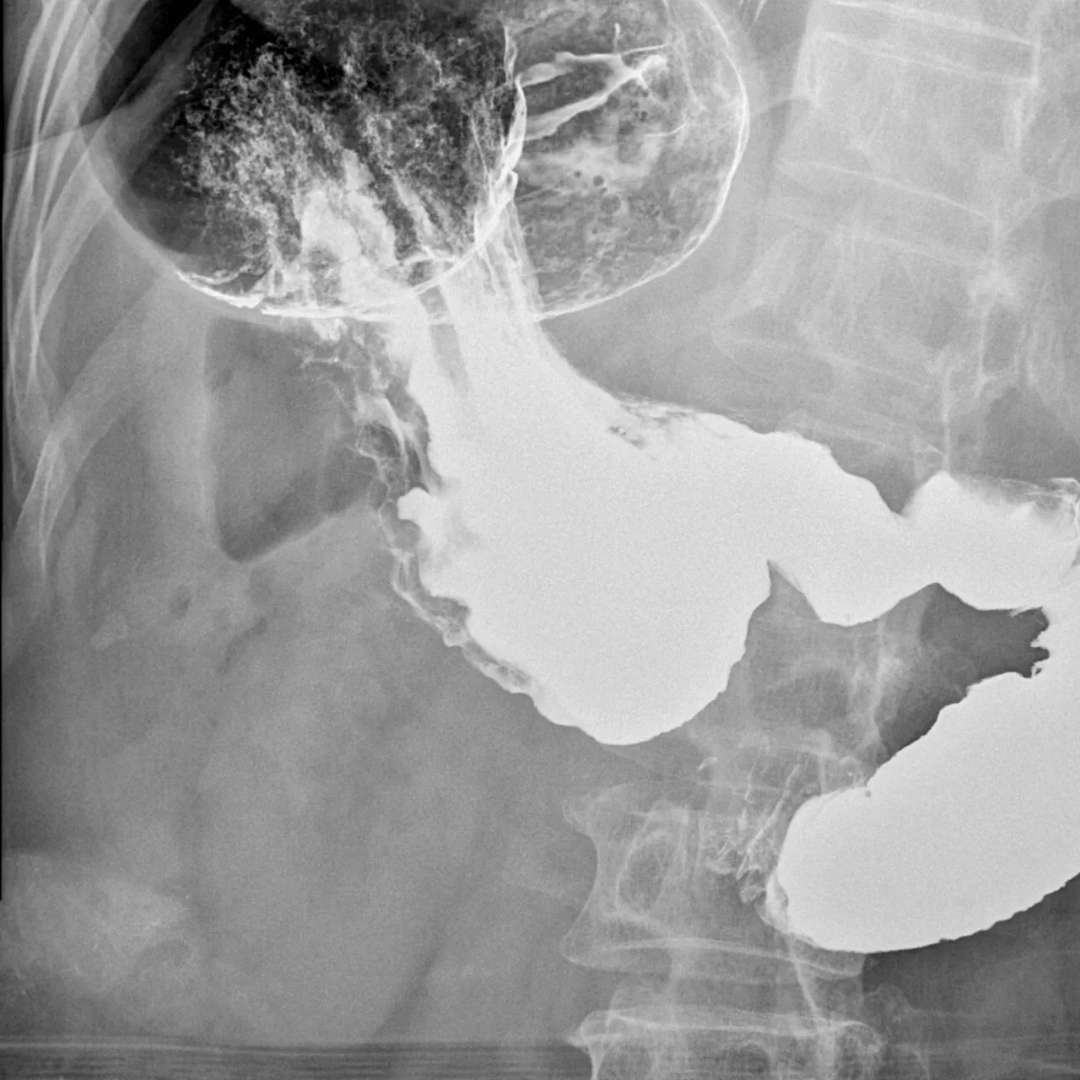

辅助检查:血、大小便及心电常规正常。免疫过筛、肝功能等正常。上腹部CT平扫未见异常。纤维胃镜示表浅性糜烂。上消化道气钡双重造影示:食管、胃腔、十二指肠上段、降段显影正常。十二指肠水平部造影剂停滞不前,呈“笔杆”状截断,改变体位后,胃腔蠕动数次后造影剂迅速通过水平部截断处。

诊断:肠系膜上动脉压迫综合症。外科给予十二指肠空肠吻合术。